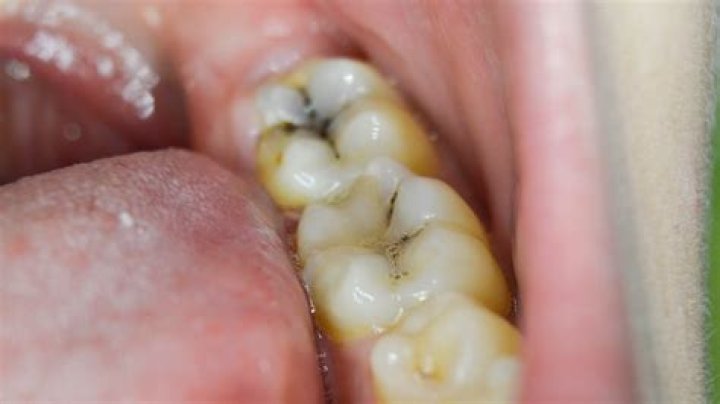

Often a cavity will look like a dark spot on the tooth, typically yellow, brown, or black in color. Early on, it may resemble tooth staining or a slight discoloration. As cavities progress, the holes get bigger and usually darker.

Cavities vary greatly in appearance. In general, however, they appear as small holes, chips or dark spots on teeth. The holes can be as small as dots or as large as the entire tooth. Sometimes they look brown, yellow or black.

What does early stage cavity look like?

Does a black spot on tooth mean cavity?

Cavity, or tooth decay: Perhaps the most common cause for a black spot on your molar teeth is tooth decay, or a cavity. A cavity forms when the build-up of plaque, which contains acids, is allowed to erode the surface enamel of a tooth. A hole in the tooth's protective layer sometimes shows as a black dot.